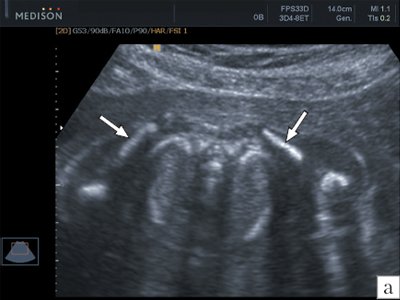

Особенности УЗИ при определении пола ребенка

Раздел: Идеи и советы